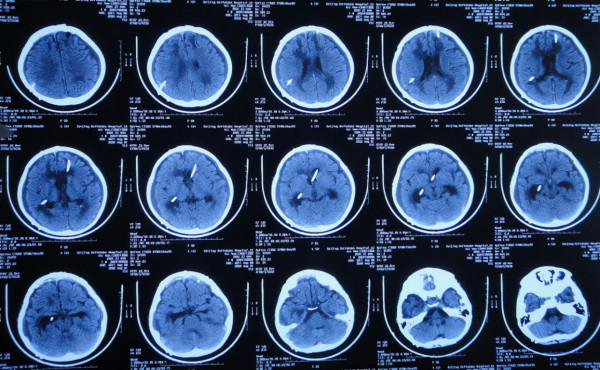

入院當天頭部CT示右側顳角擴張,腦室內有3根管(圖-33)。

圖-33:2020年5月19日頭部CT

入院後第3天即2020年5月21日,拔除了原腦室引流管和Ommaya囊+左側腦室外引流術和右側顳角引流術(圖-34)。

圖-34:2020年5月21日頭部CT